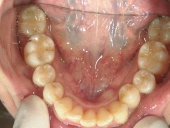

矯正歯科 治療後

矯正歯科 治療後 下顎